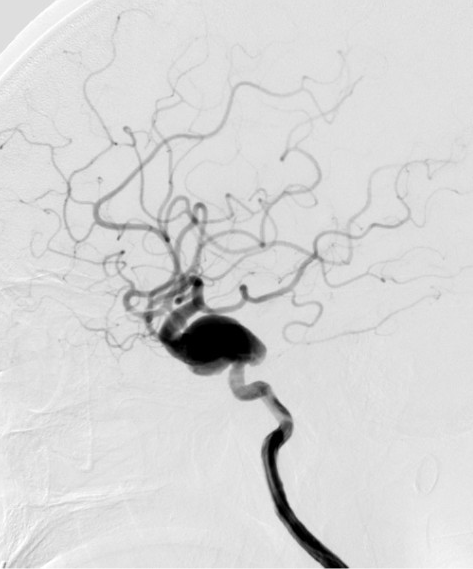

- 新路图下,沿微导管依次填入数枚弹簧圈,将动脉瘤填塞。复查造影证实动脉瘤达完全栓塞,载瘤动脉通畅。

动脉长鞘怎么置入深谋远路 | 千人皆翘首,万唤今始来——国内首款7F长鞘在血流导向密网支架联合弹簧圈栓塞治疗动脉瘤的首次应用_https://www.jmylbn.com_新闻资讯_第27张术后正位造影

术后侧位造影